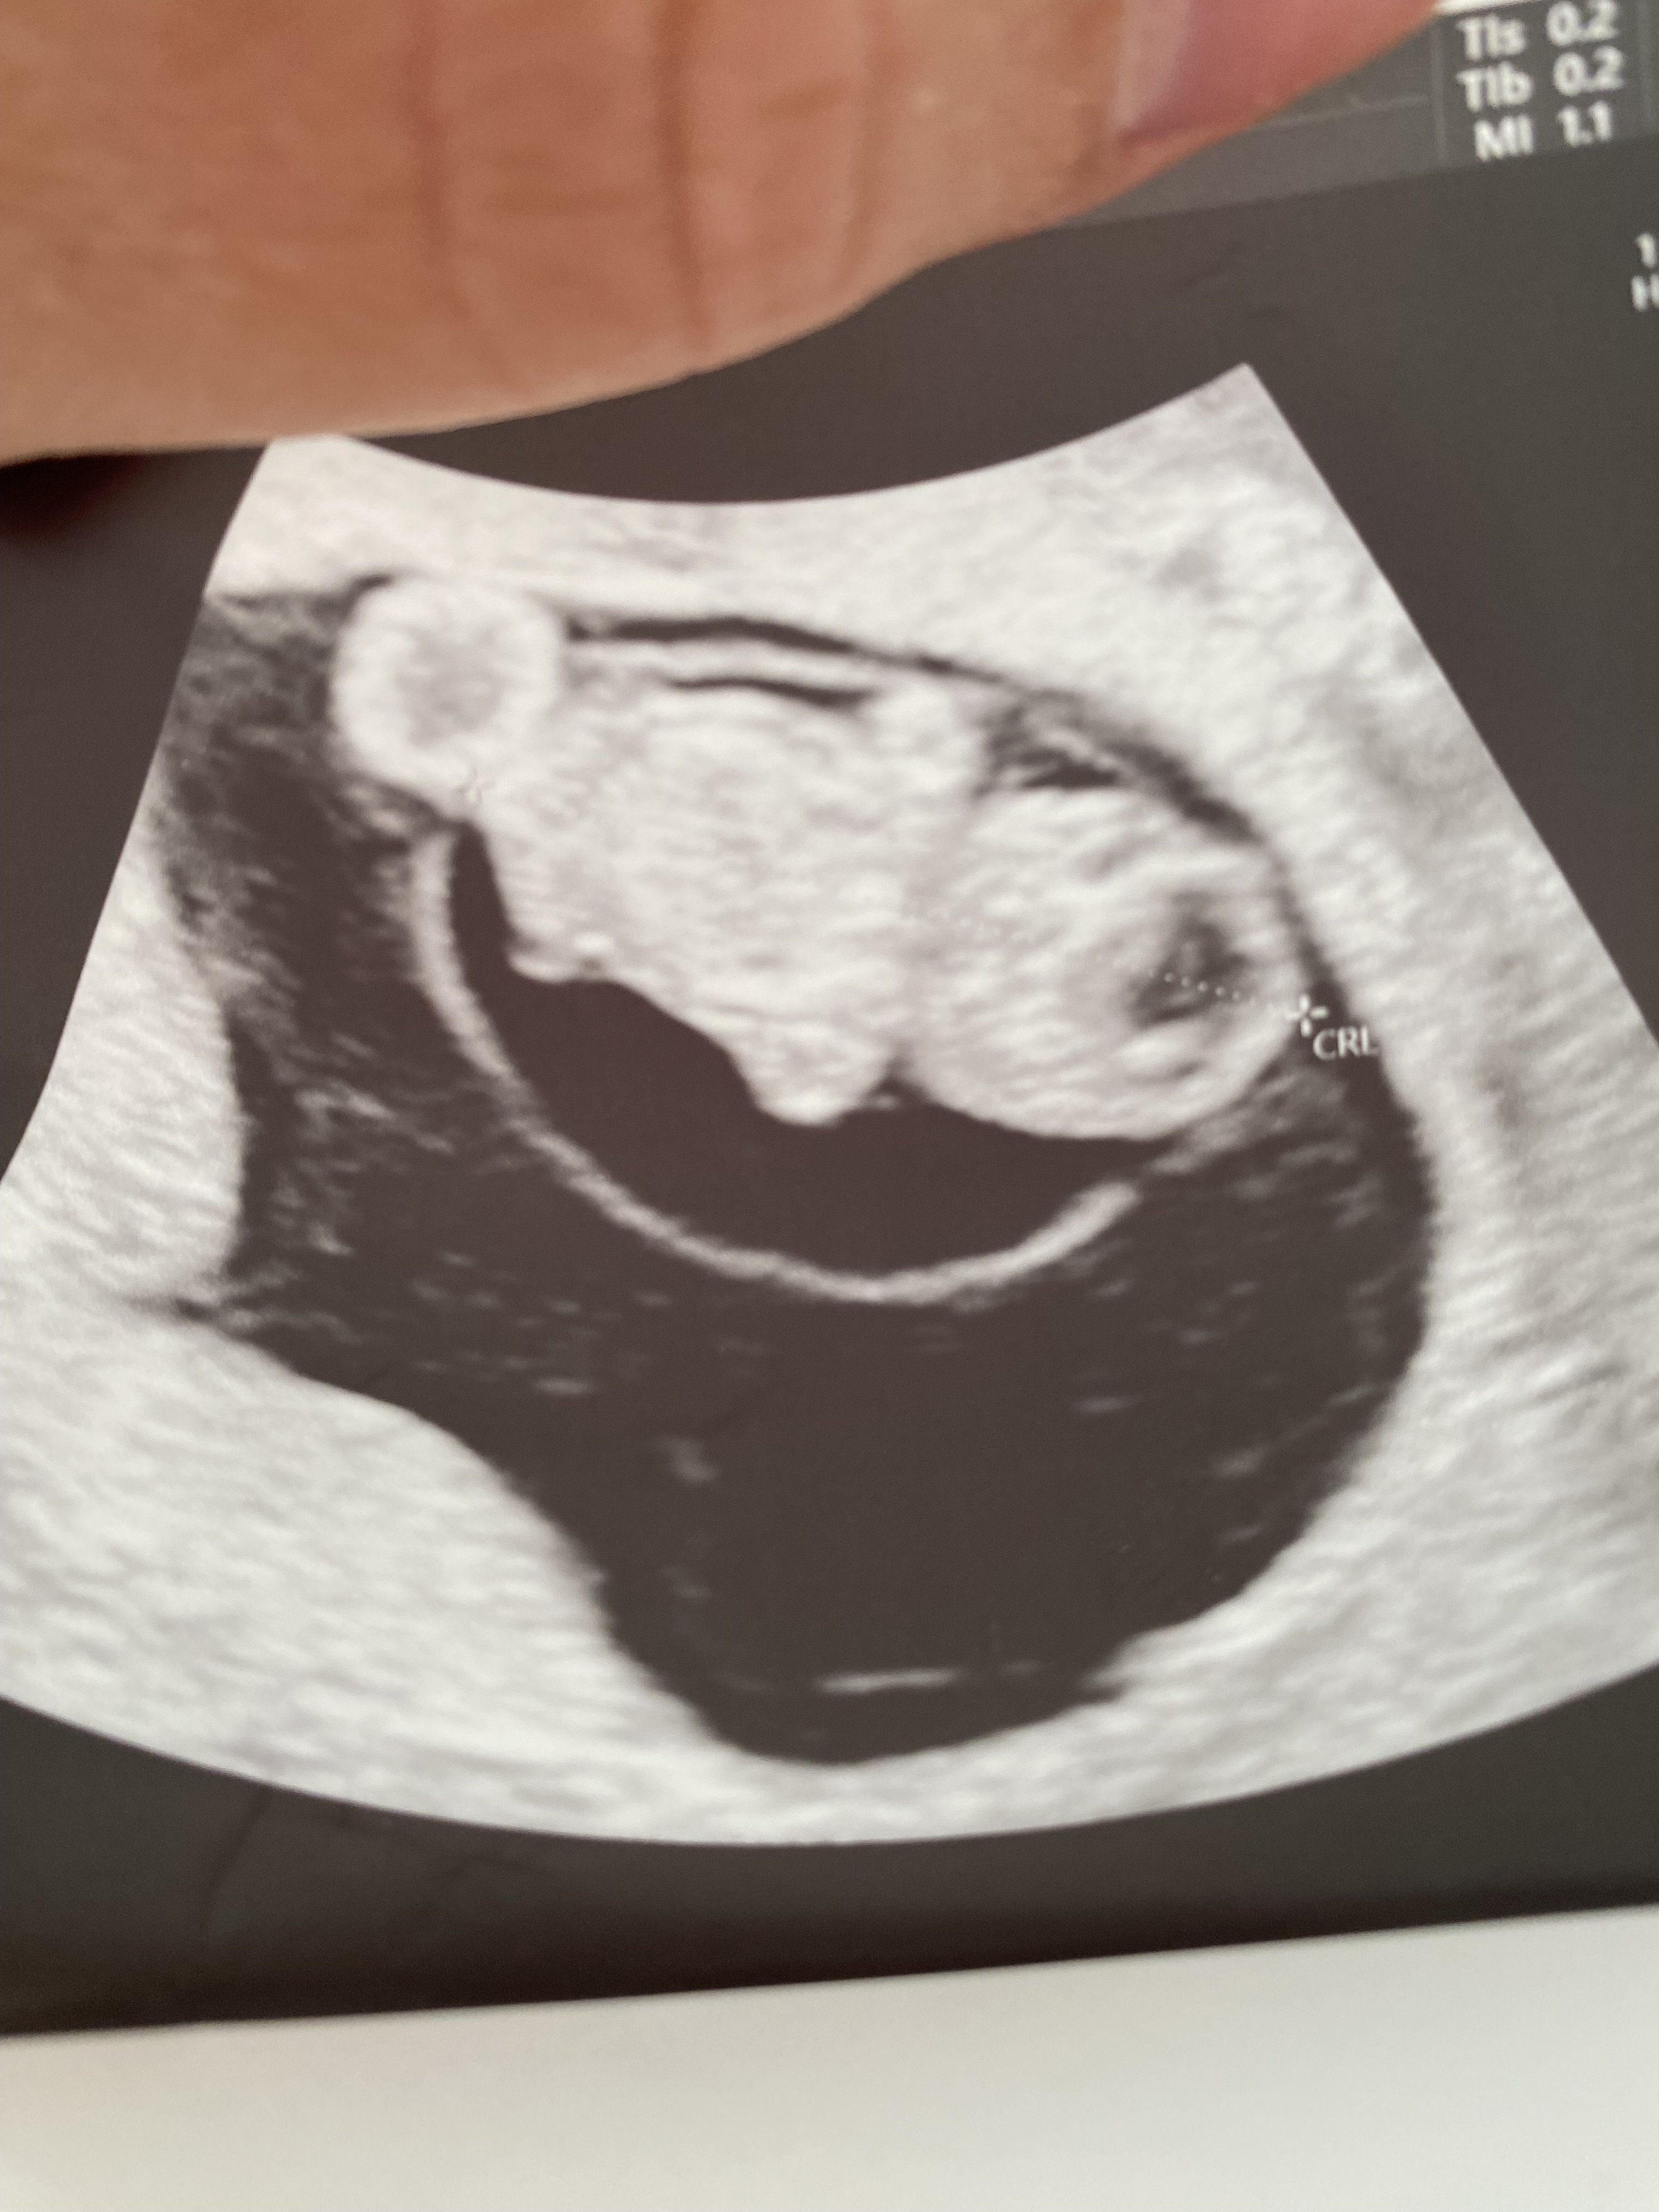

Jestem po wizycie 🤩

Moje malutkie bobo ma calutkie, okrąglutkie 2 cm 🥹🥹🥹😍

Serduszko 175

• IMG_4187.jpeg

IMG_4187.jpeg

1,1 MB · Wyświetleń: 84